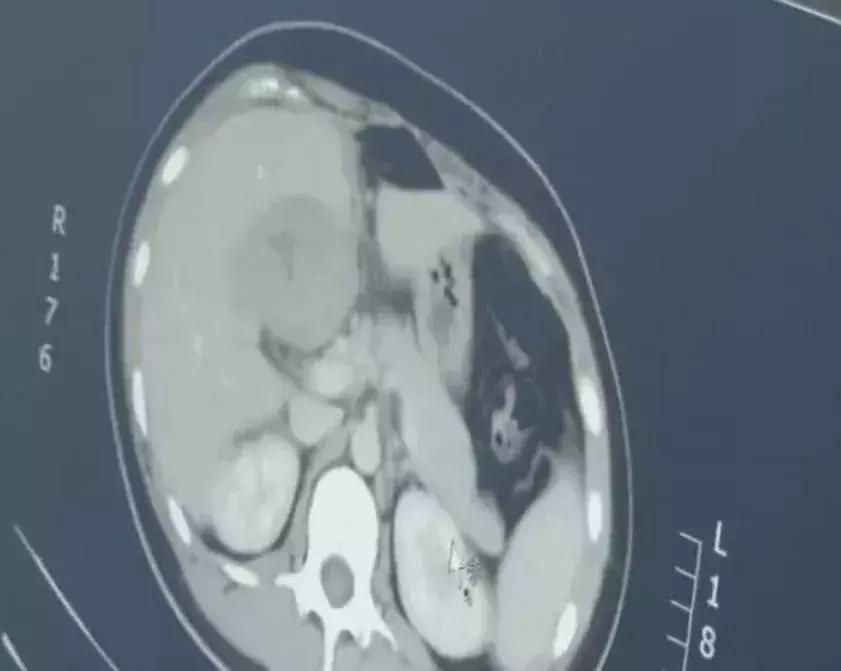

问题来了,那孩子呢?医生立刻想到了宫外孕,于是给尤女士做了CT,最后竟然在肝脏部位,找到了胚胎……

连见多识广的医生都感叹:这是一个罕见的宫外孕病例!

据介绍,宫外孕常见于输卵管附近,胚胎跑到肝脏部位极为罕见,很容易引发大出血,危及生命。

医生当天通过腹腔镜手术,为患者去除了危险的包块。